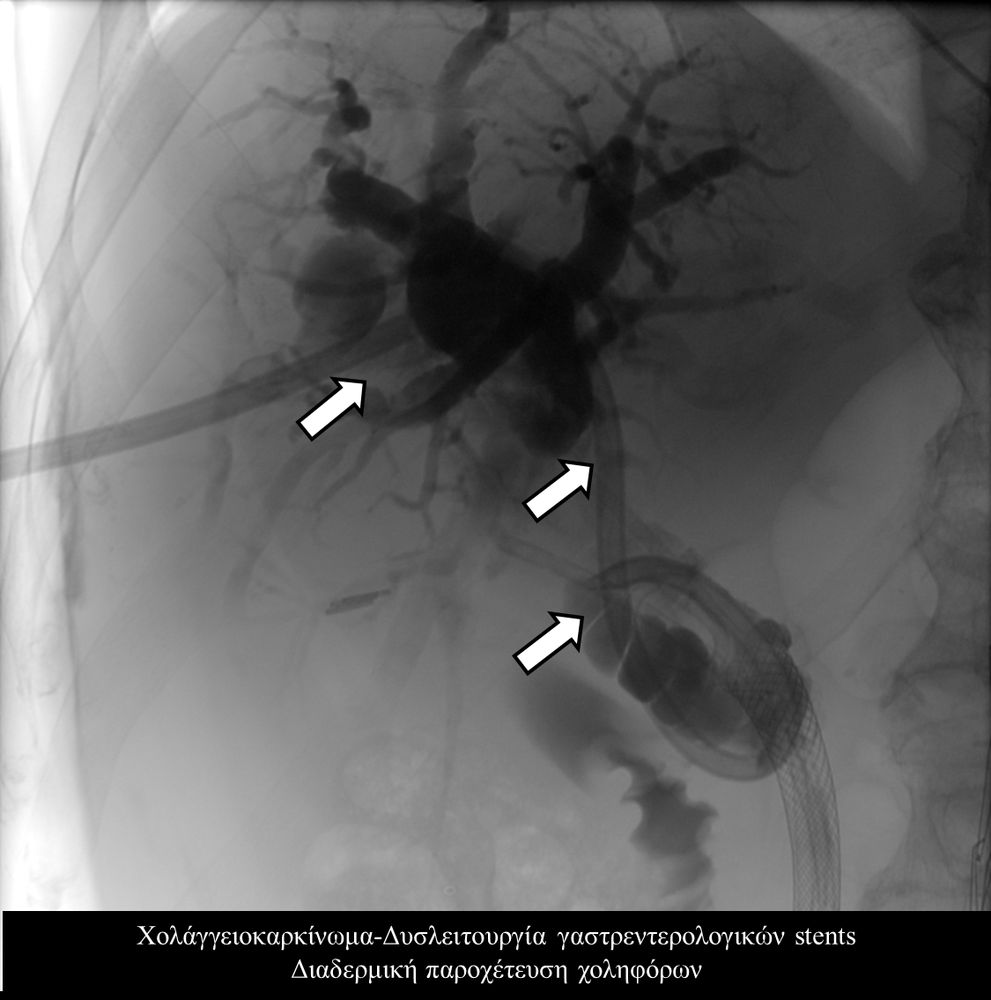

Σε πολλές περιπτώσεις πρωτοπαθών ή δευτεροπαθών όγκων ήπατος - παγκρέατος προκαλείται απόφραξη των χολαγγείων με συνοδό αποφρακτικό ίκτερο.Ο ασθενής με αποφρακτικό ίκτερο δεν μπορεί να υποβληθεί σε χημειοθεραπεία, αν δεν αποκατασταθεί ο ίκτερος με παροχέτευση των χοληφόρων.

Η παροχέτευση των χοληφόρων σε αυτές τις περιπτώσεις θα πρέπει να γίνεται άμεσα, είτε ταυτόχρονα προς τα έξω και προς το 12κτυλο (έσω-έξω παροχέτευση), είτε μόνο προς τα έξω με τη βοήθεια pigtailκαθετήρα (εξωτερική παροχέτευση)

Σε περιπτώσεις όπου υπάρχει απόφραξη των χοληφόρων και ενδείκνυται η τοποθέτηση ενδοπρόθεσης (stent), τότε η βατότητα των χολαγγείων και η αντιμετώπιση του αποφρακτικού ικτέρου μπορεί να διασφαλιστεί με την τοποθέτηση ενδοπροθέσεων (stents).

Η προσπέλαση σε όλες τις περιπτώσεις γίνεται διαδερμικά και η νοσηλεία του ασθενούς διαρκεί συνήθως μία ημέρα και ο ασθενής επιστρέφει στο σπίτι του την επομένη.